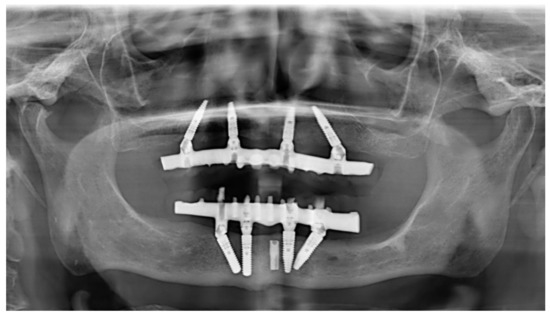

On the day of definitive prosthesis placement, new maxillary acrylic resin occlusal nightguards were delivered to each patient and screw access openings were restored with a provisional material (Fermit, Ivoclar Vivadent, Naturno, Bolzano, Italy). The patients were recalled every 4 months for professional oral hygiene and peri-implant parameter recording (BoP and PS) and every 12 months for annual radiographic and clinical examinations, following the EAO guidelines [35] (Figure 8).

Figure 8.

Panoramic radiograph after 7 years of use in maxillary-implant-supported rehabilitation. In the mandible, the same treatment was performed with standard-diameter implants. One previously placed implant had fractured and was left in the subgingival region. It was not included in the rehabilitation treatment.